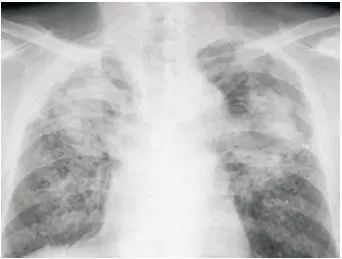

粉塵沉積的肺部X光造影 網絡配圖